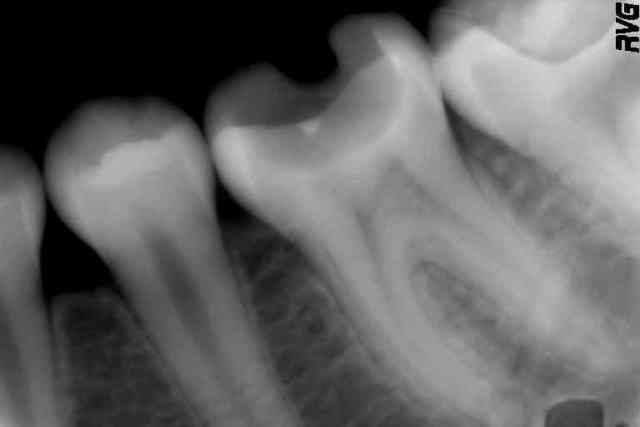

Je relance le sujet, car c'est exactement ce qui vient de m'arriver 2 fois de suite. Même histoire pour les deux dents : un gros composite bien propre, assez récent, très douloureux à la mastication. Je dépose le composite sous anesthésie : cavité bien nette. Pose de Biodentine. Réévaluation au cours d'une autre séance prévue pour autre chose, puis compo lors d'une troisième séance.

Ca marche quand même bien, dans cette indication.

A quoi ça sert de faire un coiffage directe sur une dent comme ça, déjà bien calcifié au niveau des racines.

La dent finira quand même par se nécroser, sauf qu'elle sera bien plus difficile à traiter endodontiquement parlant.

Préserver la vitalité lorsque la dent est immature, je veux bien ; mais là je ne vois pas trop l'intérêt de garder la dent "vitale" ou "semi vitale" quelques mois de plus...